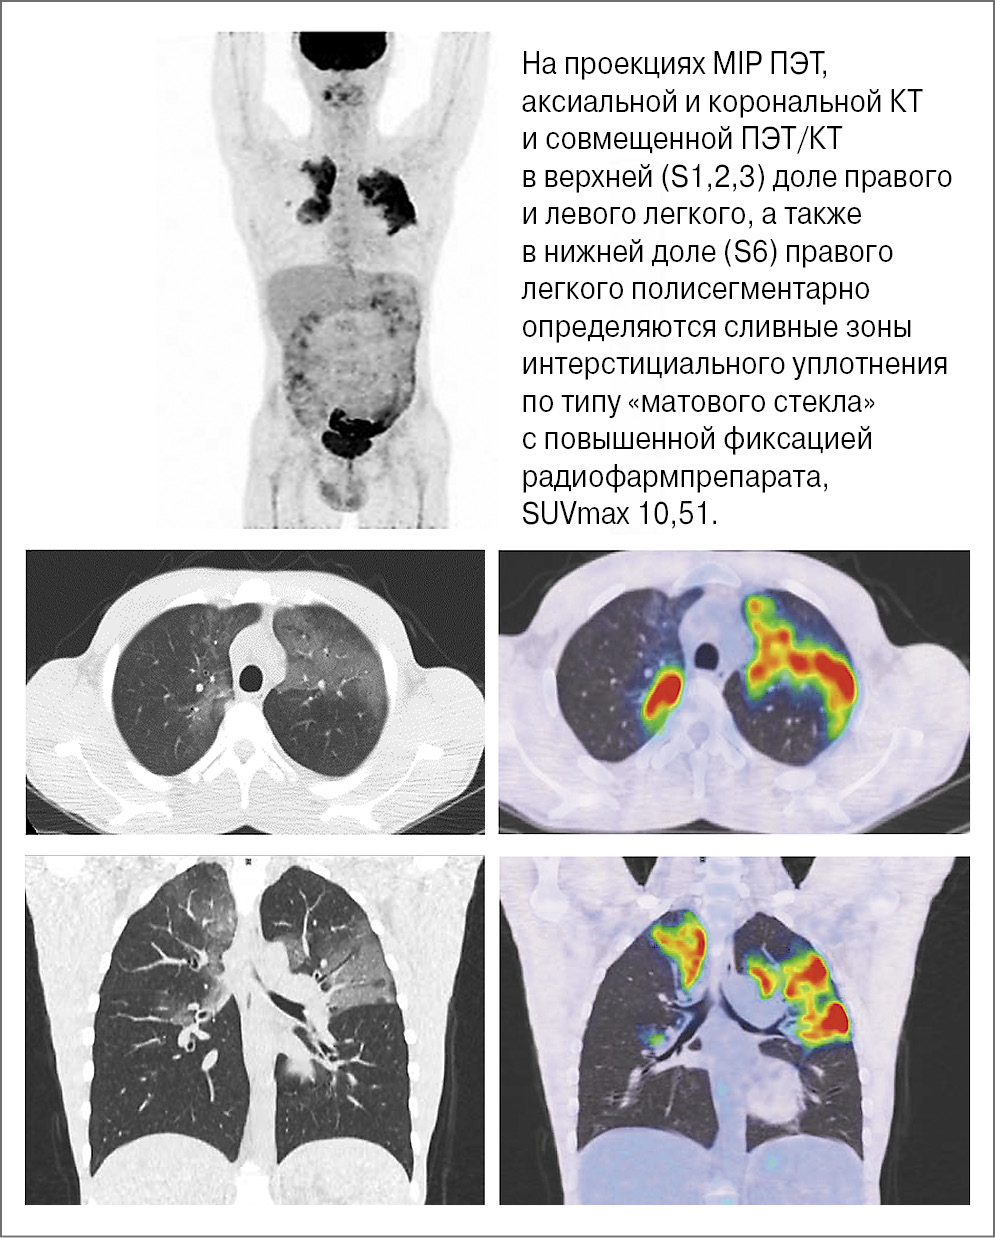

Рис. 1. Пациент П., 37 лет. Через 12 мес после начала поддерживающей терапии ритуксимабом.

Через 7 нед после последнего введения ритуксимаба (24 мес) по результатам очередной ПЭТ/КТ с 18F-ФДГ выявлены диффузные интерстициальные уплотнения по типу «матового стекла» в правом и левом легком с повышенной фиксацией радиофармпрепарата легочной тканью. Коэффициент SUVmax равнялся 10,51. Признаков прогрессирования опухолевого процесса не обнаружено. Указанные изменения расценены как интерстициальный пневмонит (рис. 2).

Рис. 2. Пациент П., 37 лет. Через 7 нед по окончании поддерживающей терапии (2 года) ритуксимабом.

В представленном случае диагноз интерстициального пневмонита установлен с помощью ПЭТ/КТ с 18F-ФДГ, по результатам которой выявлены зоны интерстициального уплотнения по типу «матового стекла» с обеих сторон с повышенной фиксацией радиофармпрепарата, SUVmax 10,51.

ПЭТ/КТ с 18F-ФДГ является методом выбора для диагностики легочной токсичности при злокачественных новообразованиях. Она позволяет диагностировать ранние проявления интерстициального заболевания легких до клинической реализации и рентгенологических изменений. Согласно полученным данным коэффициент стандартизированного максимального поглощения радиофармпрепарата SUVmax легочной тканью составил 10,51.